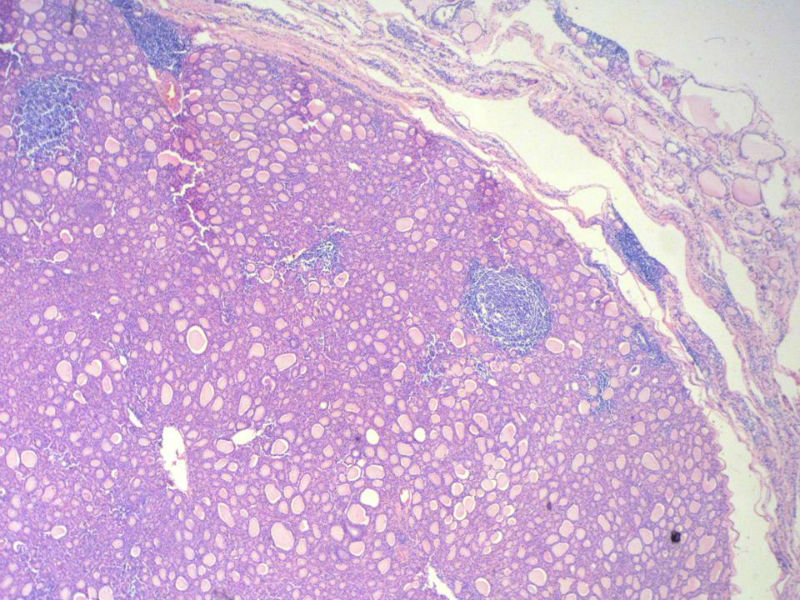

女,60岁,右侧甲状腺肿物两个月,术中见肿块与周围组织无粘连,肉眼,灰红色组织,3X2X2厘米,切面见一直径2.5厘米肿物,包膜完整,灰黄色,质软。

具有桥本氏病的大部分特征,有结节形成,此情况有称之为“结节性桥本甲状腺炎”